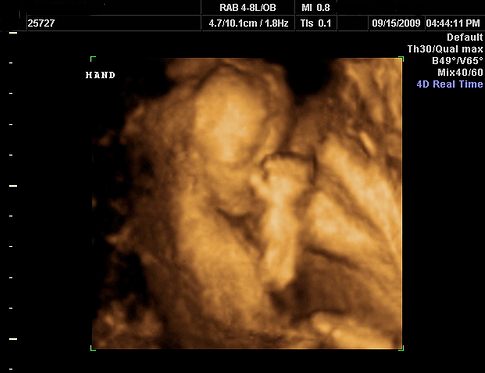

According to the AP, Attorney General Drew Edmonson let a state judge block a law that requires all women seeking an abortion to get an ultrasound first. Not just any ultrasound: “The law requires doctors to use a vaginal probe, which provides a clearer picture of the fetus than a regular ultrasound, and to describe the fetus in detail, including its dimensions, whether arms, legs and internal organs are visible and whether there is cardiac activity,” AP reports. “The law also requires doctors to turn a screen depicting the ultrasound images toward the woman so she can view them.”